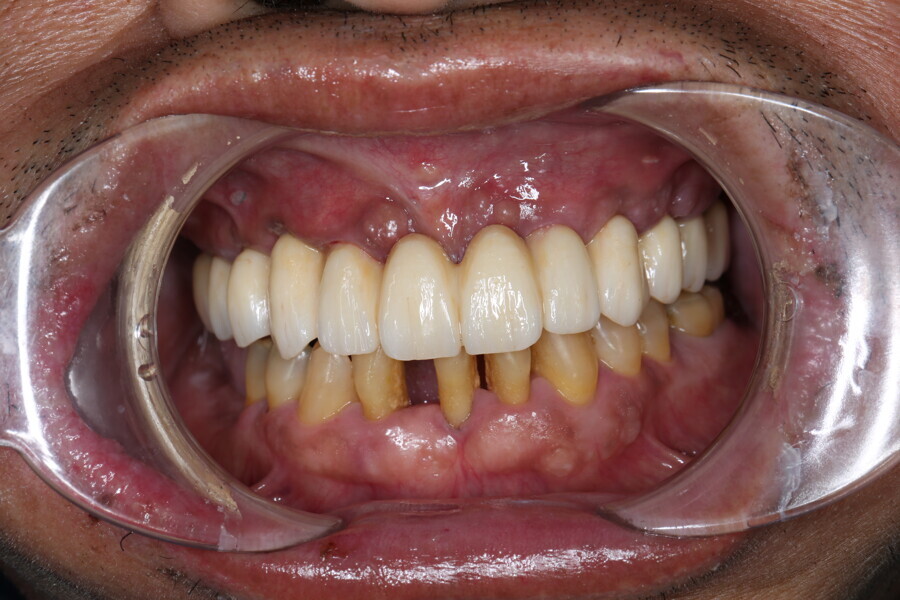

Compromised maxillary dentition treated with Straumann Pro Arch and a digital workflow